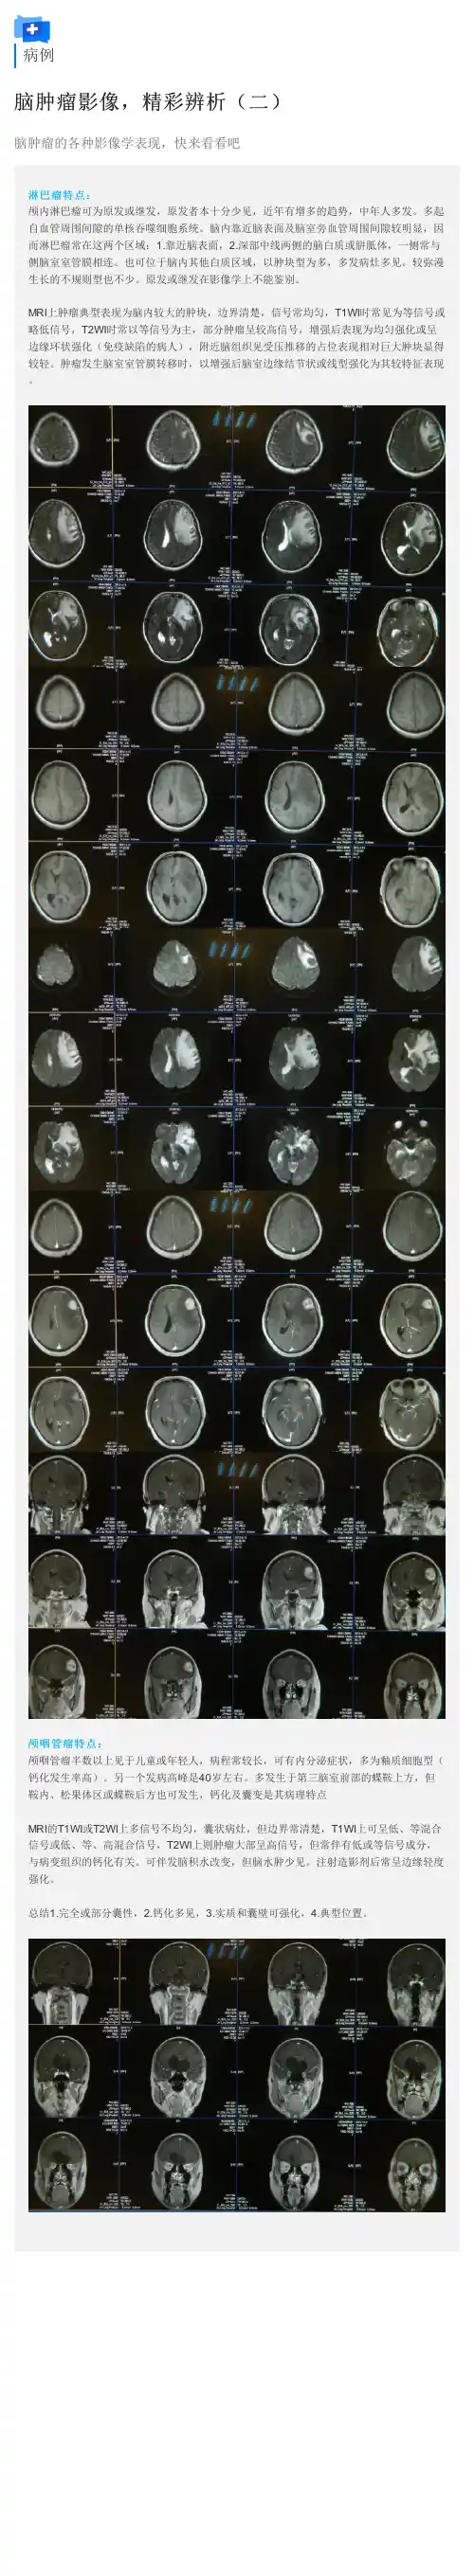

病例

脑肿瘤影像,精彩辨析(二)

脑肿瘤的各种影像学表现,快来看看吧

淋巴瘤特点:

颅内淋巴瘤可为原发或继发,原发者本十分少见,近年有增多的趋势,中年人多发。

多起自血管周围间隙的单核吞噬细胞系统。

脑内靠近脑表面及脑室旁血管周围间隙较明显,因而淋巴瘤常在这两个区域:1.靠近脑表面,2.深部中线两侧的脑白质或胼胝体,一侧常与侧脑室室管膜相连。

也可位于脑内其他白质区域,以肿块型为多,多发病灶多见。

较弥漫生长的不规则型也不少。

原发或继发在影像学上不能鉴别。

MRI上肿瘤典型表现为脑内较大的肿块,边界清楚,信号常均匀,T1WI时常见为等信号或略低信号,T2WI时常以等信号为主,部分肿瘤呈较高信号,增强后表现为均匀强化或呈边缘环状强化(免疫缺陷的病人),附近脑组织见受压推移的占位表现相对巨大肿块显得较轻。

肿瘤发生脑室室管膜转移时,以增强后脑室边缘结节状或线型强化为其较特征表现。

颅咽管瘤特点:

颅咽管瘤半数以上见于儿童或年轻人,病程常较长,可有内分泌症状,多为釉质细胞型(钙化发生率高)。

另一个发病高峰是40岁左右。

多发生于第三脑室前部的蝶鞍上方,但鞍内、松果体区或蝶鞍后方也可发生,钙化及囊变是其病理特点

MRI的T1WI或T2WI上多信号不均匀,囊状病灶,但边界常清楚,T1WI上可呈低、等混合信号或低、等、高混合信号,T2WI上则肿瘤大部呈高信号,但常伴有低或等信号成分,与病变组织的钙化有关。

可伴发脑积水改变,但脑水肿少见。

注射造影剂后常呈边缘轻度强化。

总结1.完全或部分囊性,2.钙化多见,3.实质和囊壁可强化,4.典型位置。